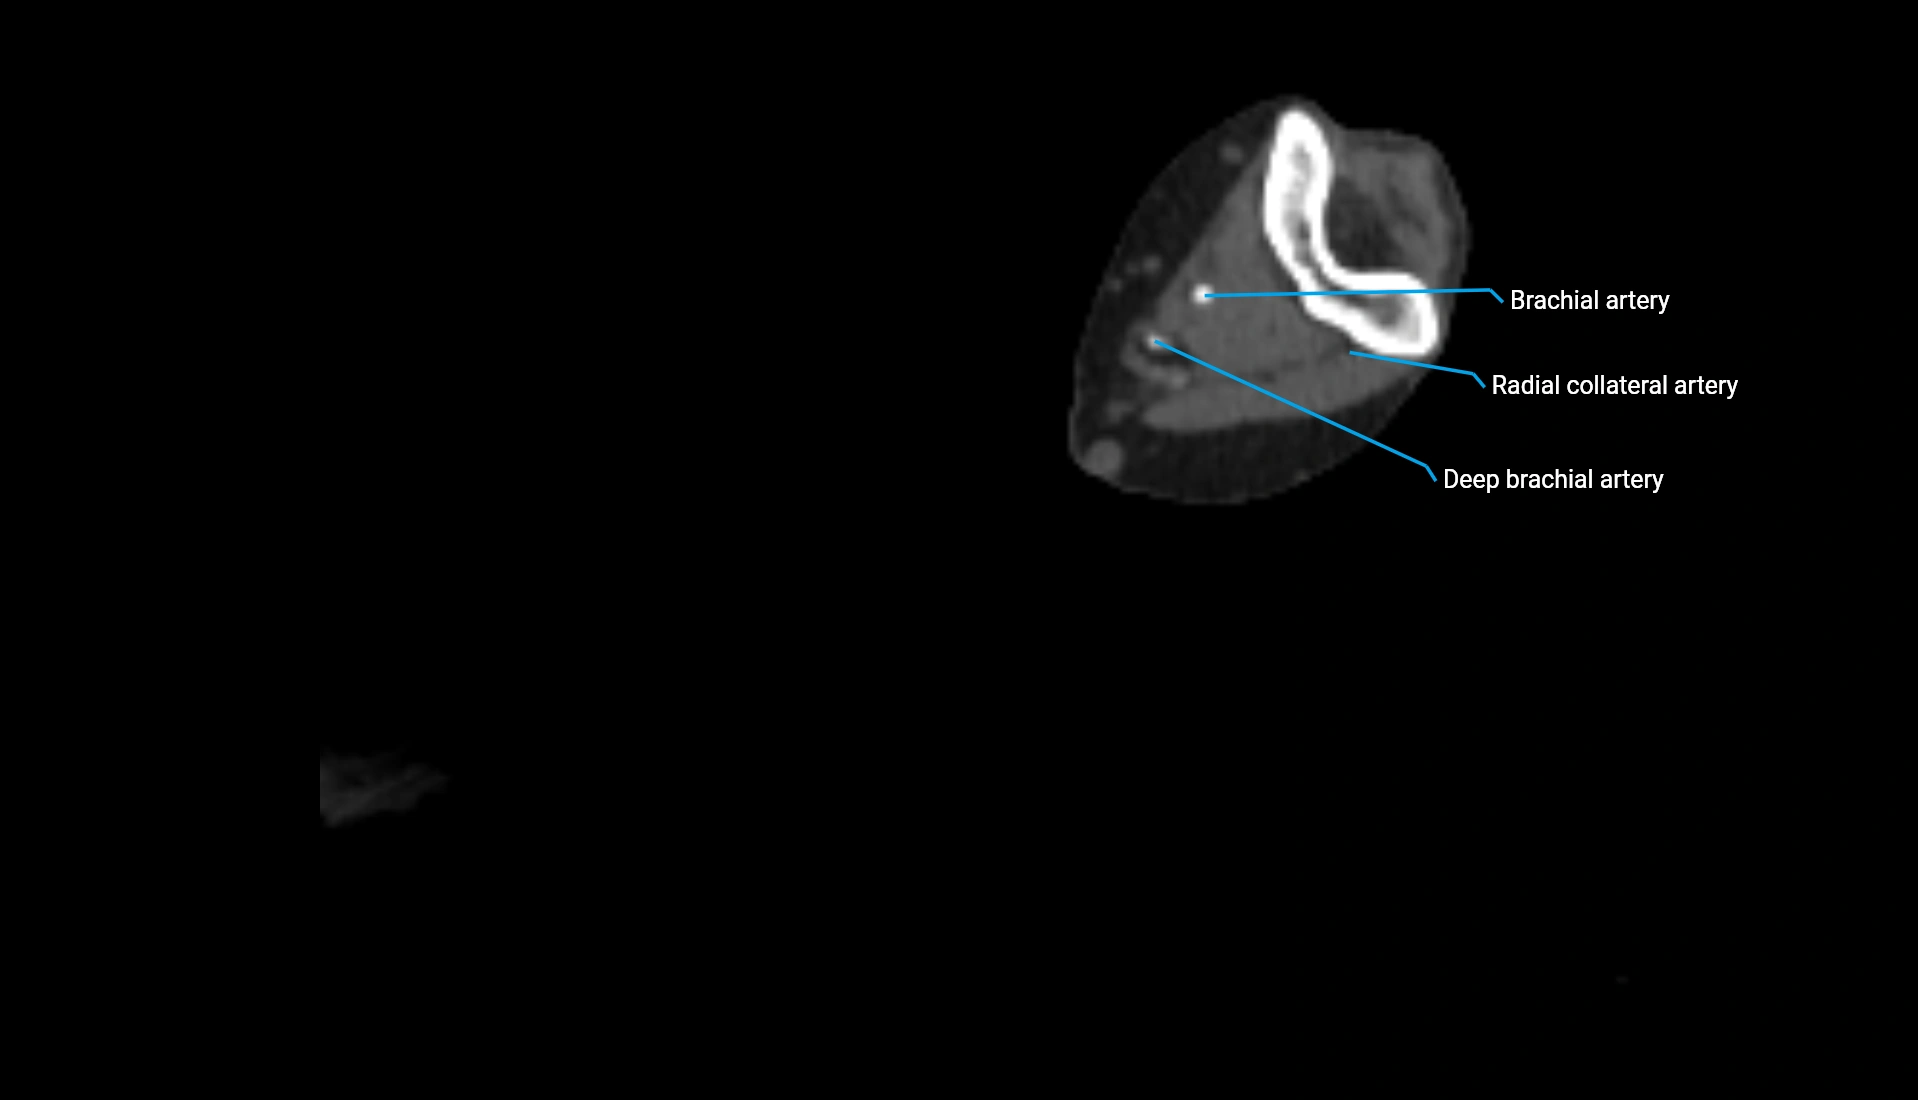

CT Appearance

Non-Contrast CT:

• Cortex: High-density, sharply defined

• Subchondral bone: Dense cancellous matrix

• Articular surface: Smooth concave contour articulating with the capitellum

• Excellent for evaluating bone integrity, alignment, and subtle fractures

Post-Contrast CT:

• Bone: No enhancement

• Joint capsule and synovium: Mild enhancement outlining the joint

• Improves contrast between soft tissues and bony margins

• Useful in detecting subtle joint abnormalities or postoperative changes